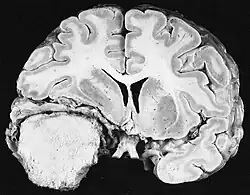

Počítačová tomografie (CT) a magnetická rezonance (MRI) mohou účinně detekovat neoplazii v mozku. MRI je citlivější než CT pro identifikaci lézí, ale má kontraindikace pro pacienty s kardiostimulátory, nekompatibilními protézami, kovovými svorkami a dalšími. CT zůstává metodou volby k detekci kalcifikací v lézích nebo kostních erozích lebky nebo spodiny. Použití kontrastních látek, které jsou v případě CT jodované a v případě MRI paramagnetické ( gadolinium ), umožňuje získat informace o vaskularizaci a integritě hematoencefalické bariéry, lepší definici nádorového nádoru ve srovnání k okolnímu edému a generování hypotéz o stupni malignity. Radiologické vyšetření také umožňuje posouzení mechanických účinků a následných změn v mozkových strukturách vyplývajících z nádoru, jako je hydrocefalus a kýla, jejichž účinky mohou být fatální. Konečně, v rámci přípravy na operaci, může být tato diagnostika použita k určení umístění léze nebo infiltrace nádoru do životně důležitých oblastí mozku. Pro tento účel je MRI účinnější než CT, protože může poskytovat trojrozměrné obrazy.

Diagnostické radiologické zobrazovací nástroje zdůrazňují změnu neoplastické tkáně ve srovnání s normálním mozkovým parenchymem (prostřednictvím změn v elektronicky zobrazené hustotě tkáně na CT a intenzitě signálu na MRI). Jako většina patologických tkání jsou nádory také rozpoznatelné podle zvýšené akumulace intracelulární vody. Na počítačovém tomogramu se jeví hypodenzní, tj. s menší hustotou než mozkový parenchym, na tomogramu nukleární magnetické rezonance s relaxací spin-mřížky hypointenzivní a při spin-spin relaxaci stejně jako protonové vážení (PD) hyperintenzivní.

Na rentgenovém snímku by oblast zdravého mozku neměla vykazovat žádnou zvláštní luminiscenci. Samozřejmostí je proto věnovat pozornost větším rozsahům kontrastního signálu.

V nádorové tkáni je obecně větší podíl zvýšení kontrastu způsoben konkrétní hematonádorovou bariérou, která umožňuje průchod jódu (CT) a gadolinia (MRI) do intratumorálního extravaskulárního intersticiálního prostoru. To zvyšuje signál (hustotu nebo intenzitu) nádoru. Je však třeba dbát na to, aby zvýšení kontrastu definitivně neodlišilo neoplazii od edému v okolí rány. Ve skutečnosti anatomicko-patologický nález v maligní infiltrující nádorové tkáni gliomu, jako u glioblastomu a anaplastického astrocytomu, se také projevuje mimo vazogenní edém způsobený destrukcí hematoencefalické bariéry nádorem. Poslední klinický stav je špatně detekovatelný diagnostickým zobrazením.

Počítačová tomografie mozku typicky ukazuje tkáňovou hmotu, která může být zesílena oběma kontrasty. Na CT se gliomy nízkého stupně obvykle jeví jako izodenzní s normálním parenchymem, a proto nemusí vykazovat zvýšení kontrastu. Podobně léze v zadní jámě lebeční, zadní jámě lebeční, je obtížné identifikovat na CT. V důsledku toho výsledky takové tomografie samy o sobě nejsou vždy dostatečné pro diagnostické účely. V pochybných případech je nezbytné použití citlivějšího zobrazování magnetickou rezonancí.

Na -MRI ukazuje intrakraniální tumor jako masivní lézi, která se po použití kontrastní látky může stát více luminiscenční. Vždy však dojde k anomálii signálu -Magnetická rezonance, která indikuje přítomnost neoplazie nebo vazogenního edému. Obvykle zvýšená luminiscence (zesílení kontrastu) svědčí pro nádor vyššího stupně malignity. Pro glioblastom je charakteristický kontrastní prstenec, jehož luminiscenční část odpovídá vitální části maligního nádoru a tmavší -hypointense oblast odpovídající nekróze tkáně.